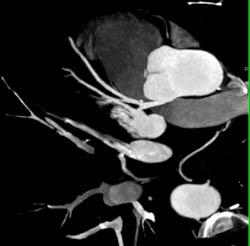

Extensive Aortic Valve Calcification With Aortic Stenosis